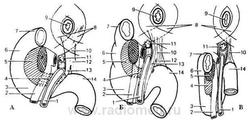

Дуоденоеюнальный переход удерживается в своем положении прочной вертикально расположенной связкой Трейтца (рис. 2.3). Эта связка содержит пучки гладких мышечных волокон, берущих начало из циркулярного мышечного слоя кишки в месте ее крутого перегиба. Связка направляется вверх и несколько вправо, позади поджелудочной железы, веерообразно расширяется и прикрепляется у устья верхней брыжеечной артерии, чревного ствола и левой ножки диафрагмы, вплетаясь в волокна покрывающего их листка предпозвоночной фасции. Анатомические варианты двенадцатиперстной кишки и связки Трейтца представлены на рисунке 2.4.

Рис. 2.4. Анатомические варианты двенадцатиперстной кишки и связки Трейтца.

(по П. А. Романову с соавт. 1986г)

А - нормодуоденум; Б - долиходуоденум; В - дуоденоптоз. 1 - верхняя брыжеечная артерия; 2 - верхняя брыжеечная вена; 3 - нижний изгиб ДПК; 4 - крючковидный отросток поджелудочной железы; 5 - головка поджелудочной железы; 6 - нисходящая часть ДПК; 7 - верхняя часть ДПК; 8 - ножки диафрагмы; 9 - пищевод; 10 - связка Трейтца; 11 - чревный ствол; 12 - левая ножка связки Трейтца; 13 - правая ножка связки Трейтца; 14 - дуоденоеюнальный переход.